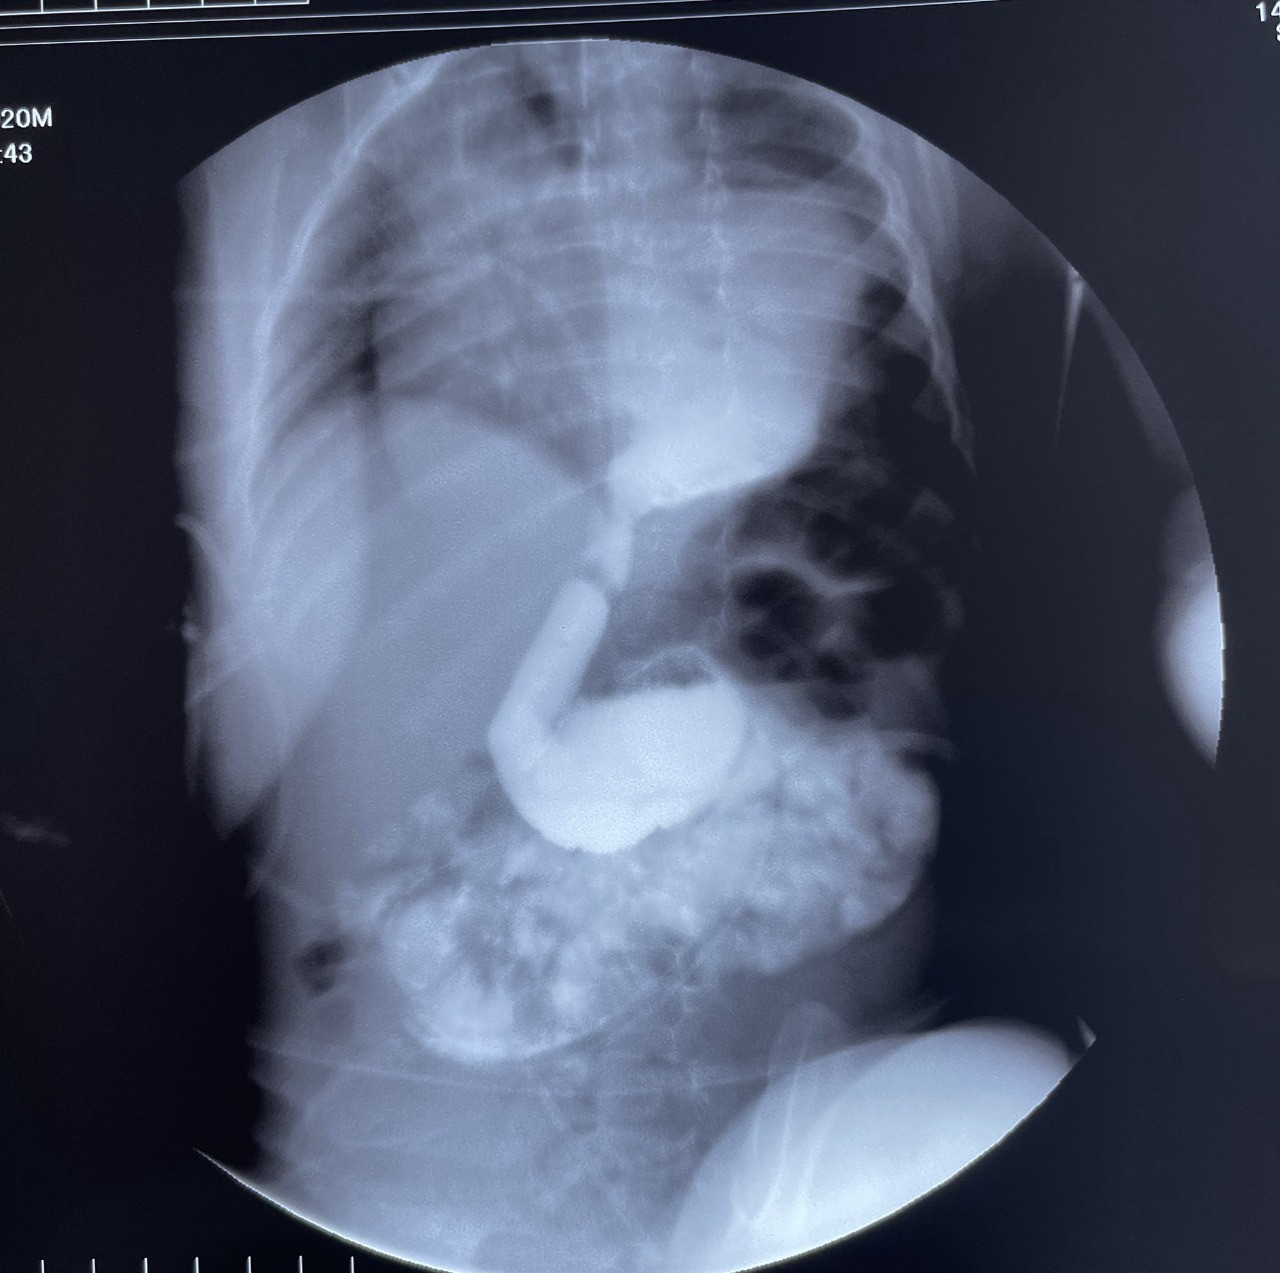

Lent.az-ın məlumatına görə, qida borusunun fistulsuz atreziyası (qida borusunun böyük qisminin anadangəlmə olmaması) ilə doğulmuş uşağa yenidoğulan dövrdə uşaq cərrahı Gündüz Ağayev tərəfindən Ezafaqo və Qastrostomiya əməliyyatı icra olunub.

1 il müddətində mədəyə qoyulmuş rezin boru ilə qidalanan uşaq 1 yaşında növbəti cərrahi əməliyyat üçün "Leyla Medical Center"ə gətirilib və xəstəyə yenə Rusiya Federasiyasının tibb elmləri doktoru Gündüz Ağayev tərəfindən, bu qüsur zamanı Azərbaycanda ilk dəfə olaraq qida borusunun əvəzlənməsi əməliyyatı icra edilib. Əməliyyatda mədə arxa divararalığından, ürəyin, aortanın və traxeyanın arxasından boyuna çıxarılaraq, qida borusunun ucu ilə birləşdirilib.

Doğulandan ağızdan qida qəbul etməyən uşaq əməliyyatdan sonra 1 ay müddətində qismən ağızdan, qismən də nazik bağırsağa yerləşdirlimiş zondla qidalanıb. Udmağı öyrəndikdən sonra ağızdan tam qidalandığına görə, nazik bağırsağa qoyulmuş zond xaric edilib.